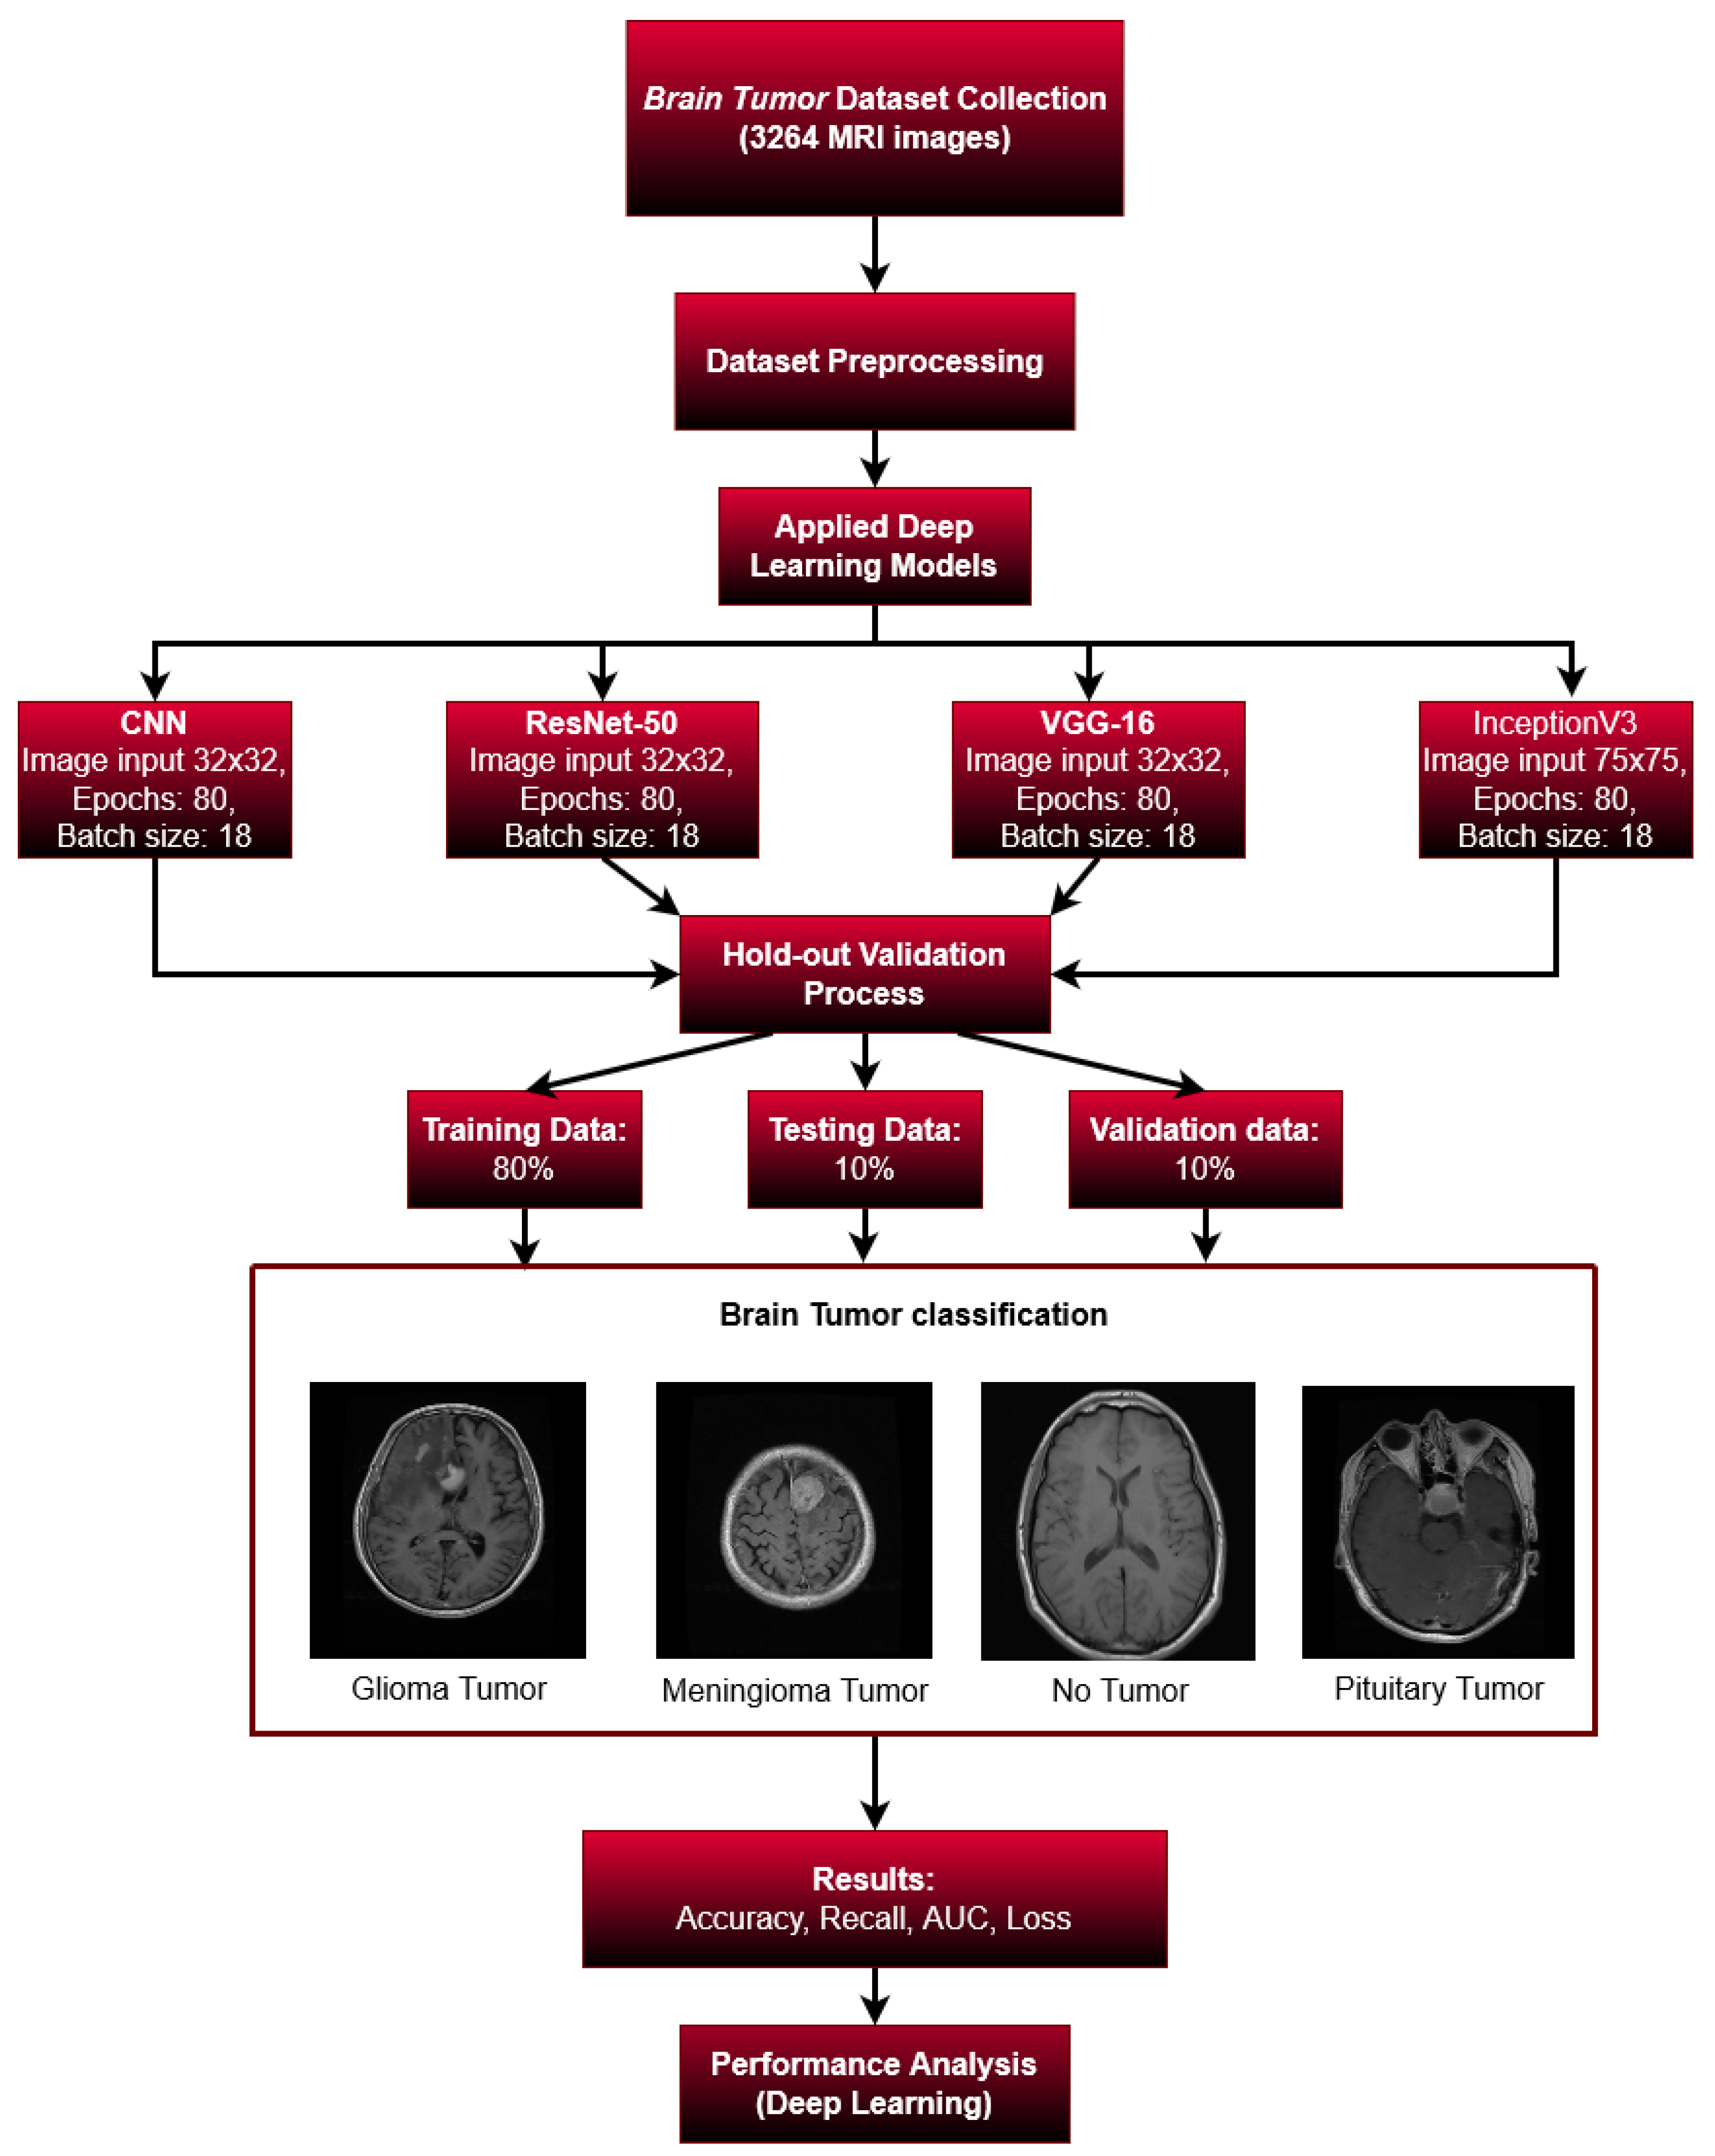

The methodology is divided into a few important stages. First, we collected our data from an available online source (kaggle.com (accessed on 10 November 2022)), then we pre-processed our datasets. We used the holdout validation system in the validation stage. We applied various machine learning models to train our images. Our dataset was split into three groups: 80% for training, 10% for testing, and 10% for validation. We tried to validate four different types of brain images: glioma tumors, meningioma tumors, no tumor, and pituitary tumors. Then, in order to validate our findings, we considered several types of metrics including the accuracy, recall, AUC, and loss. Figure 3 shows the step-by-step breakdown of this research.

Figure 3.

Overall Study.